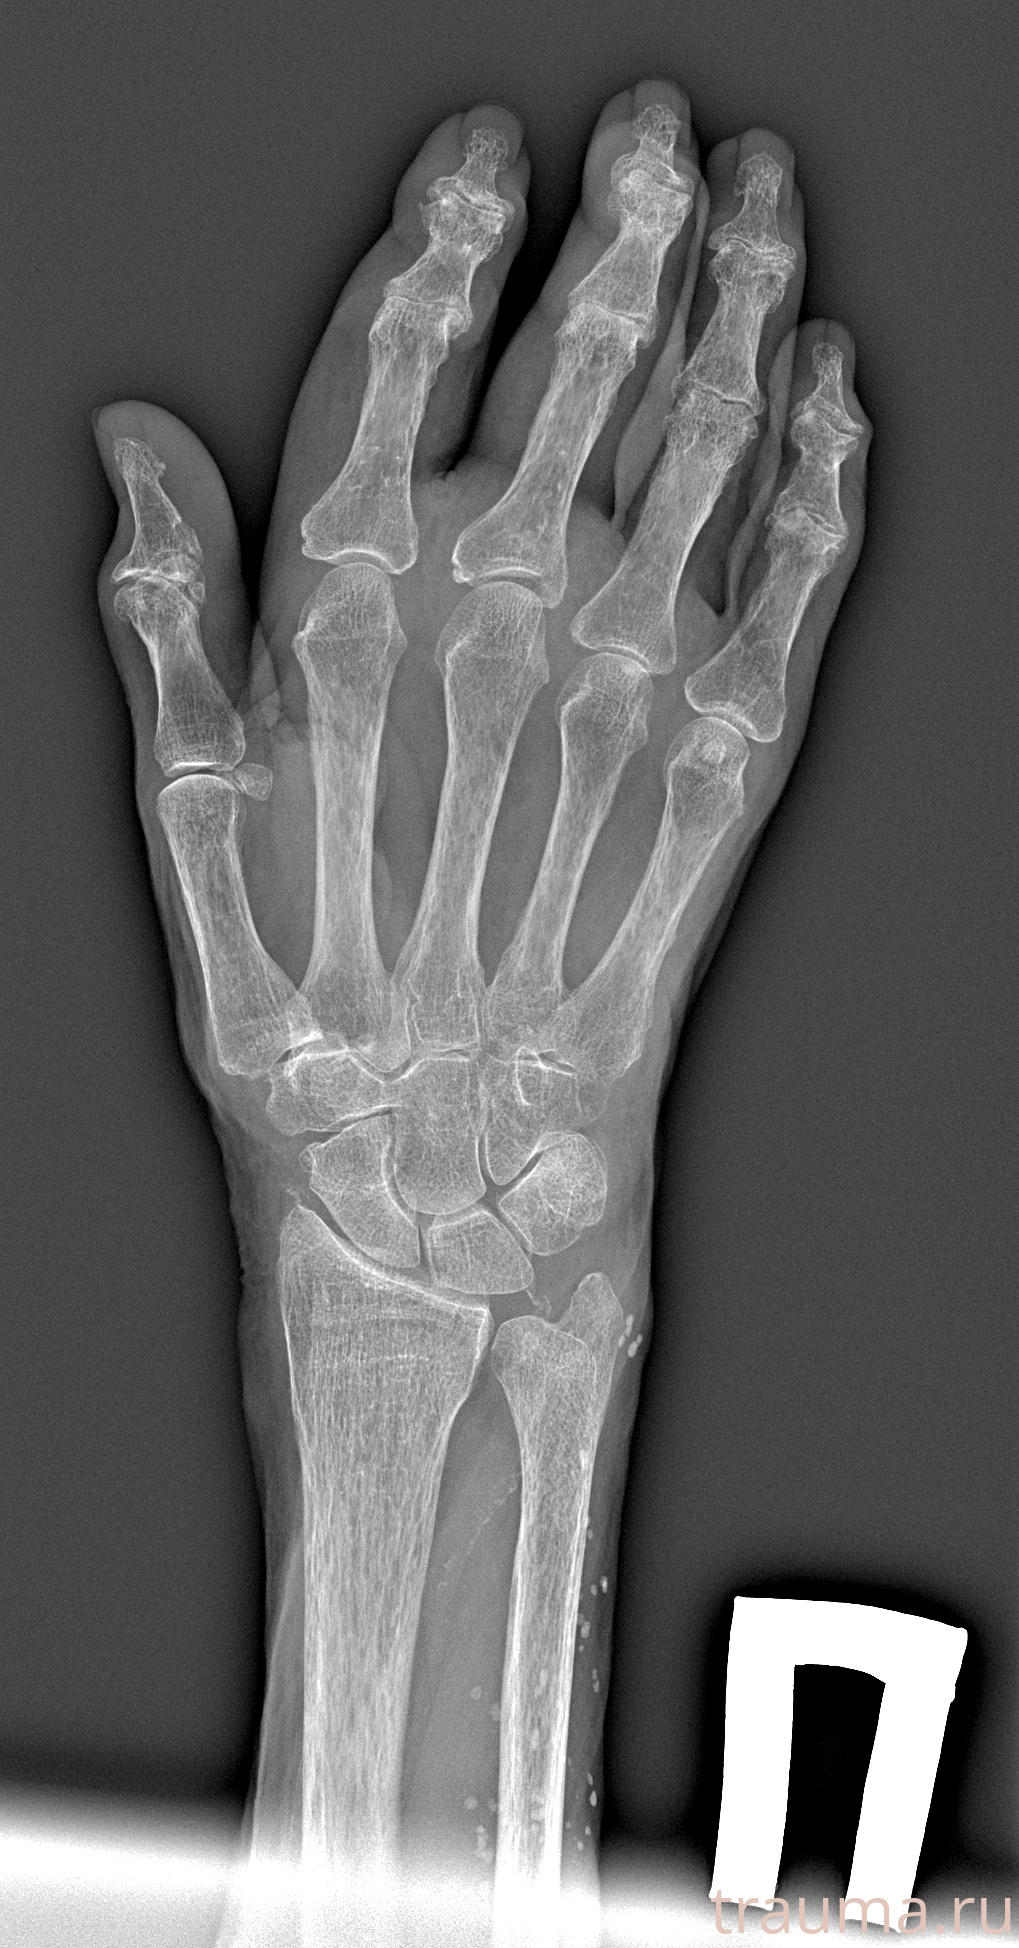

Рентгенограммы

Рентген на дому: по вашему адресу приезжает врач-рентгенолог, травматолог-ортопед с мобильным рентгеновским аппаратом, проводит диагностику травмы или заболевания, делает необходимые рентгенограммы, дает рекомендации по дальнейшему лечению. Получить качественные снимки в домашних условиях возможно благодаря уникальной методике, разработанной МосРентген Центром для института  Склифосовского